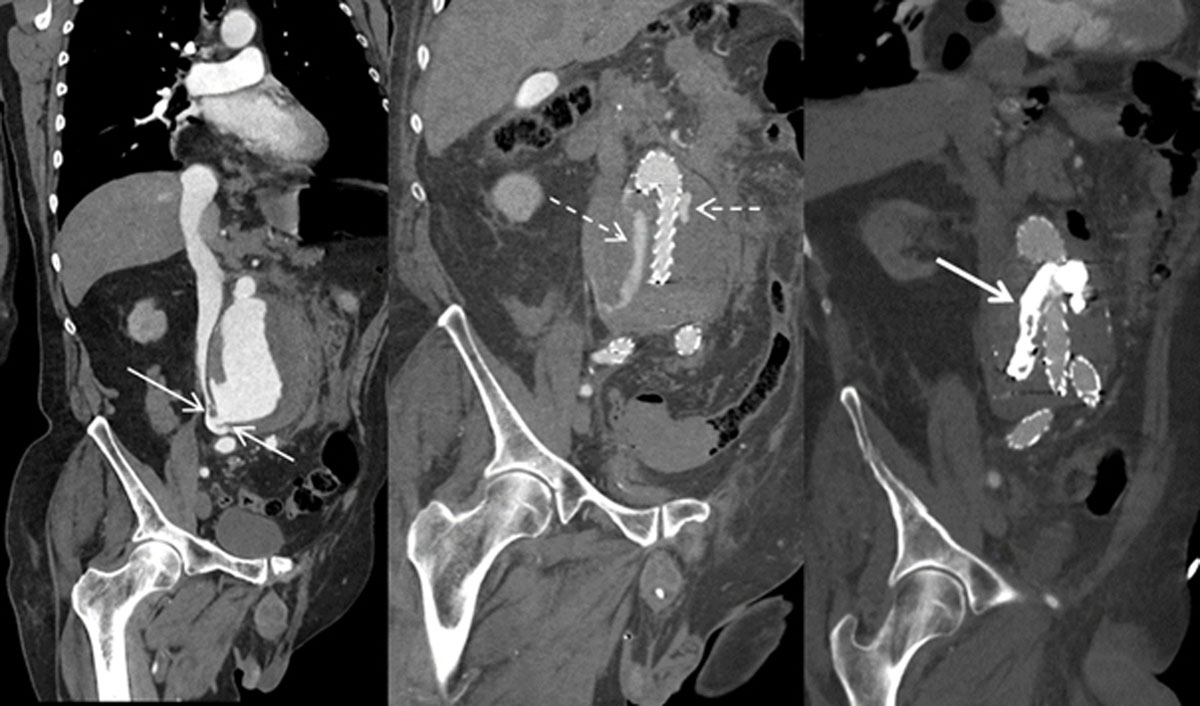

Prompt endovascular aortic repair was performed. On a post-surgery CT scan, an endoleak type 1 was depicted. The leak was subsequentially embolized with cyanoacrylate glue (Figures 2 and 3: arrows ACF, dashed arrows endoleak, bold arrows cyanoacrylate glue).

Figure 2

Figure 3